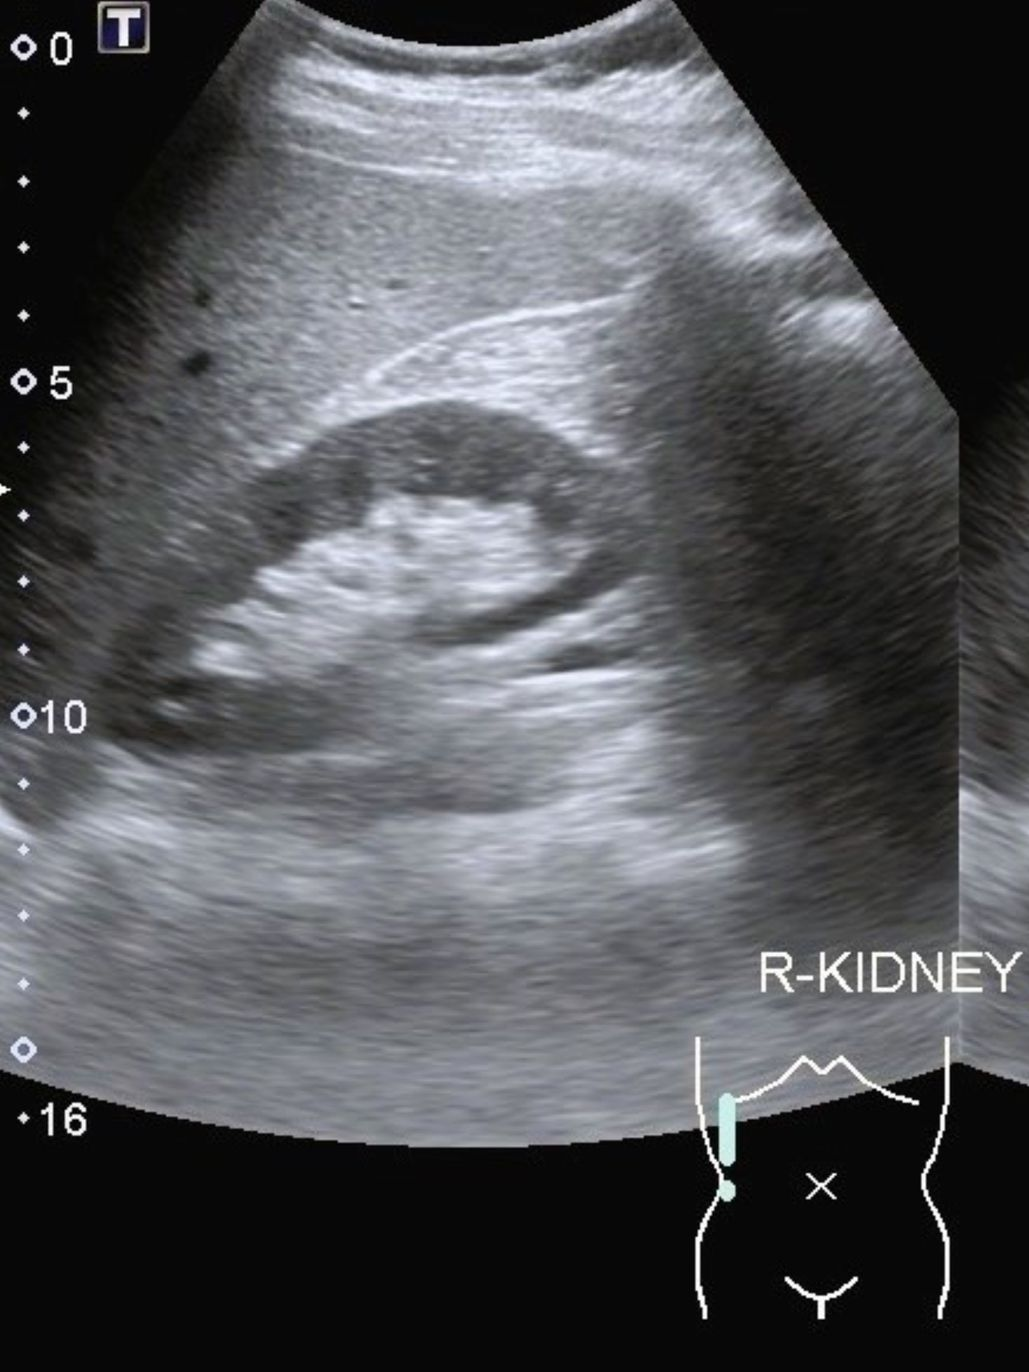

L’échographie rénale est une méthode d’imagerie médicale non invasive qui repose sur l’utilisation des ultrasons pour visualiser les reins et les voies urinaires.

Au Centre de radiologie Victor Hugo à Paris 16ᵉ, cet examen est réalisé à l’aide d’une sonde échographique, appliquée sur la peau au niveau de l’abdomen ou des flancs.

L’échographie rénale permet de détecter des anomalies telles que des calculs, des kystes, des infections ou des malformations.

Elle met en lumière les obstructions et la dilatation des voies urinaires, les calcifications et les dysplasies rénales.

L'échographie est totalement indolore, sans rayonnement. Grâce à des équipements de pointe, le Centre de radiologie Victor Hugo garantit une qualité d’image optimale pour un diagnostic précis et rapide.